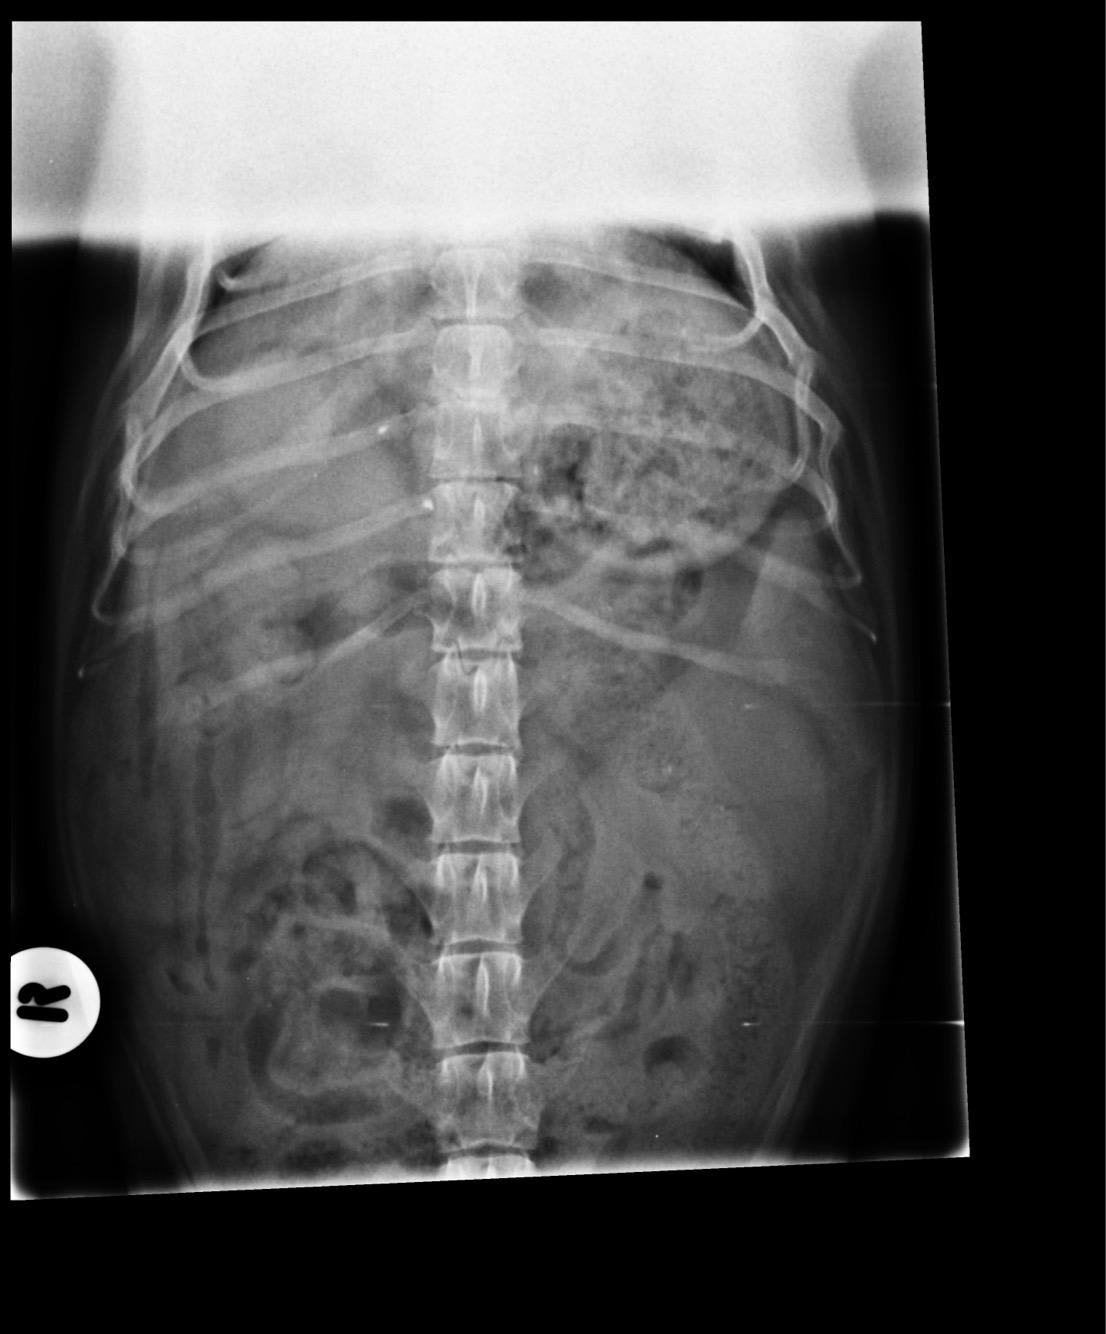

Pet's info: Dog | Dachshund | Male | neutered | 6 years and 6 months old | 20 lbs

Could you please let me know what you think could be in the X-rays? We did a biopsy and I have also attached the report. Please say if you feel it could be removed as well. What would be your next step?

The biopsy results are inconclusive, as they were unable to definitively diagnose what the mass is. This is often the case with bleeding masses in the abdomen - biopsies are often non-diagnostic, due to the fact that there is so much associated hemorrhage, which it looks like is basically all they were able to tell on the biopsy. It's likely that the only way an accurate diagnosis will be achieved is by doing an exploratory surgery of the abdomen. At that time, the mass can be visualized and completely removed (also typically the spleen as well). I recommend x-rays of the chest before this is attempted, as this is the most common site of metastasis. If there is disease in the lungs the prognosis is significantly worse, and this would likely factor into your decision to do the surgery or not.